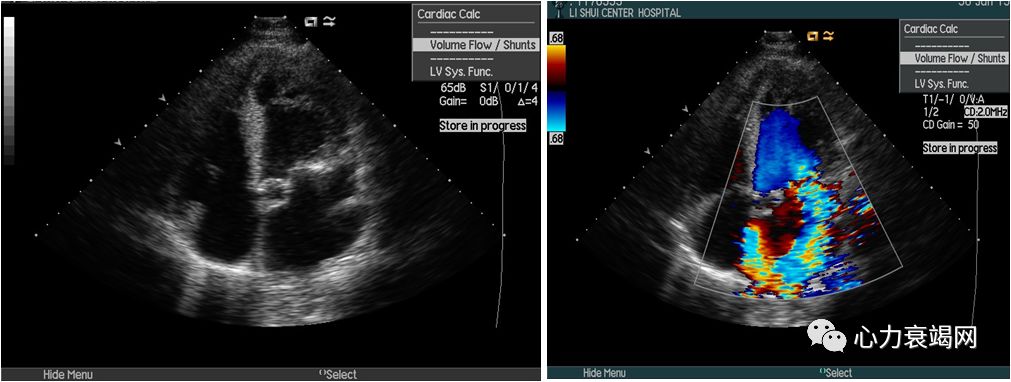

➤ 全心扩大(左房内径50mm,左室内径(d)76mm,(s)58mm)

➤ LVEF47%,肺动脉压94mmHg

➤ 二尖瓣前叶收缩期突向左房,二尖瓣收缩期见重度关闭不全

➤ 室间隔厚11mm,左室后壁厚11mm

➤ 心脏超声:

1.二尖瓣前叶裂缺伴中重度反流

2.左房室增大

3.左室下壁及前壁收缩活动减弱

4.轻度肺动脉高压

➤ 诊断:二尖瓣反流。在全麻下行二尖瓣成形术

➤ 术中经食道超声心动图检测提示:二尖瓣腱索断裂伴重度反流